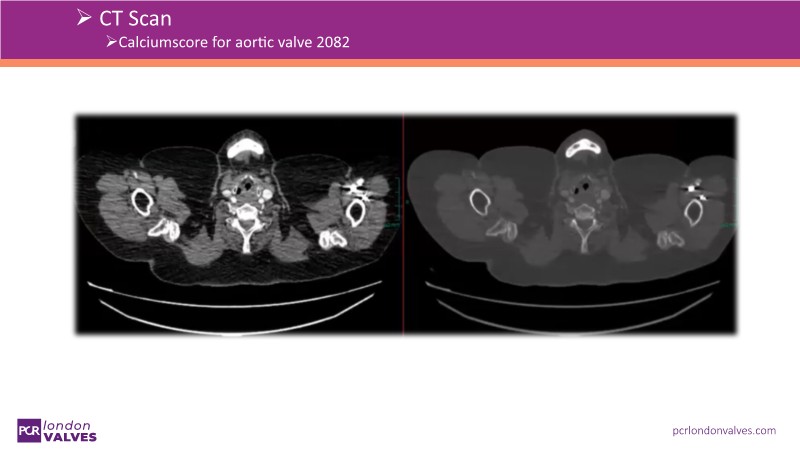

This session addresses emerging topics in structural heart disease by examining patient-centered solutions such as EVOQUE transcatheter tricuspid valve replacement (TTVR) and SAPIEN transcatheter heart valve-in-heart valve (THV-in-THV) procedures. It covers the latest data from Europe on redo TAVI, lifetime management strategies beginning with initial prosthesis planning, evolving patient selection for TTVR, and features an educational live case alongside expert panel discussions on procedure safety and efficacy.

- To understand the latest considerations and techniques for redo TAVI and get exposed to the latest data from Europe

- To learn how to maximise the benefits of TAVI with a lifetime management strategy that starts with the planning of the first prosthesis